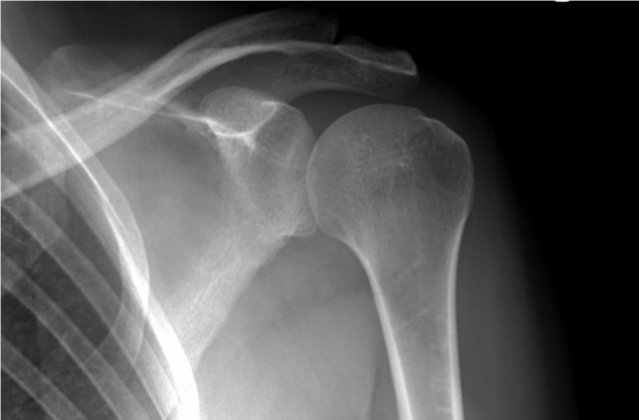

Osteopoikilosis is a hereditary bone dysplasia classified within the group of connective tissue diseases. Although it is considered a rare anomaly, it has no serious clinical implications in most cases. It is characterized by the appearance of small sclerotic (dense) lesions of oval or round shape, visible on X-rays. These lesions, which are symmetrically distributed in the long bones, pelvis, hands, feet, and scapulae, do not cause significant functional alterations or transform into malignant pathologies.

The diagnosis of osteopoikilosis is made through imaging studies, mainly X-rays. These show multiple dense, symmetrical, and well-defined lesions, ranging in size from 2 to 10 mm.

The most frequently affected areas include: Long bones such as the femur and humerus, pelvis, scapulae, small bones of the hands and feet.